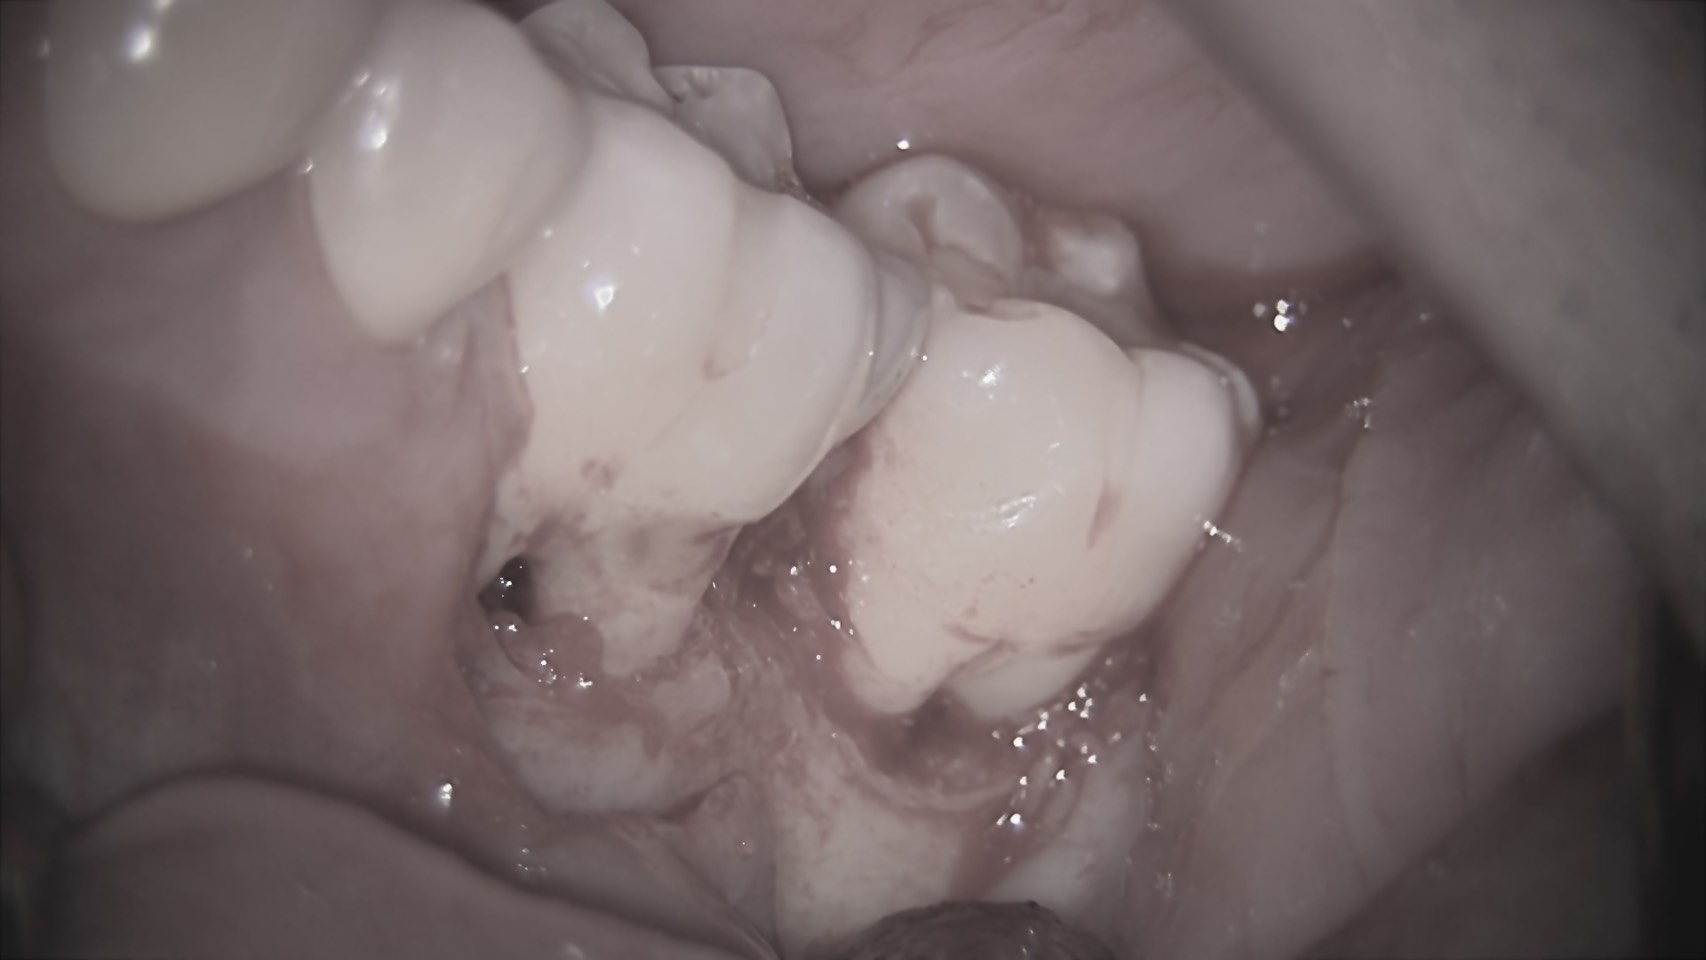

2. 手術(歯周外科処置)

麻酔を行い、歯茎を丁寧に開きます。

実際に歯茎を開いてみると、レントゲンの通り、骨が深くえぐれるように無くなっていました。ここにある歯石や感染した組織(不良肉芽)を徹底的に除去します。

3. リグロスの塗布

きれいになった骨の欠損部分に「リグロス」を塗布します。

リグロスは、細胞を増やす成長因子(bFGF)を主成分とするお薬です。これを塗ることで、失われた歯周組織(骨や歯根膜)の再生を強力に促します。

4. 縫合

最後に歯茎を元の位置に戻して縫合し、手術は終了です。